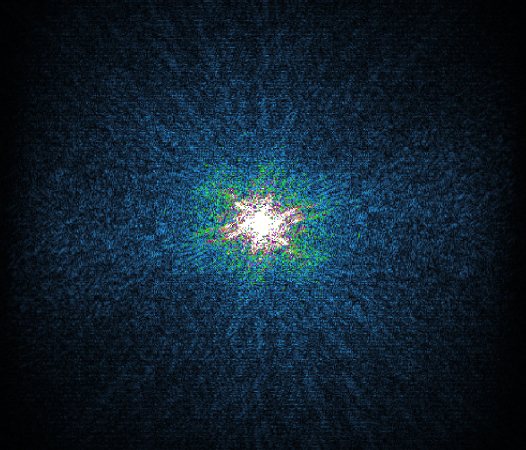

Philips Compressed SENSE

The Compressed SENSE reconstruction then uses iterative, knowledge-based algorithms to fill in the empty lines in k-space (bottom left). This removes the artifacts while keeping the final image fully consistent with the acquired data (bottom right). *Compared to Philips MR exams without Compressed SENSE